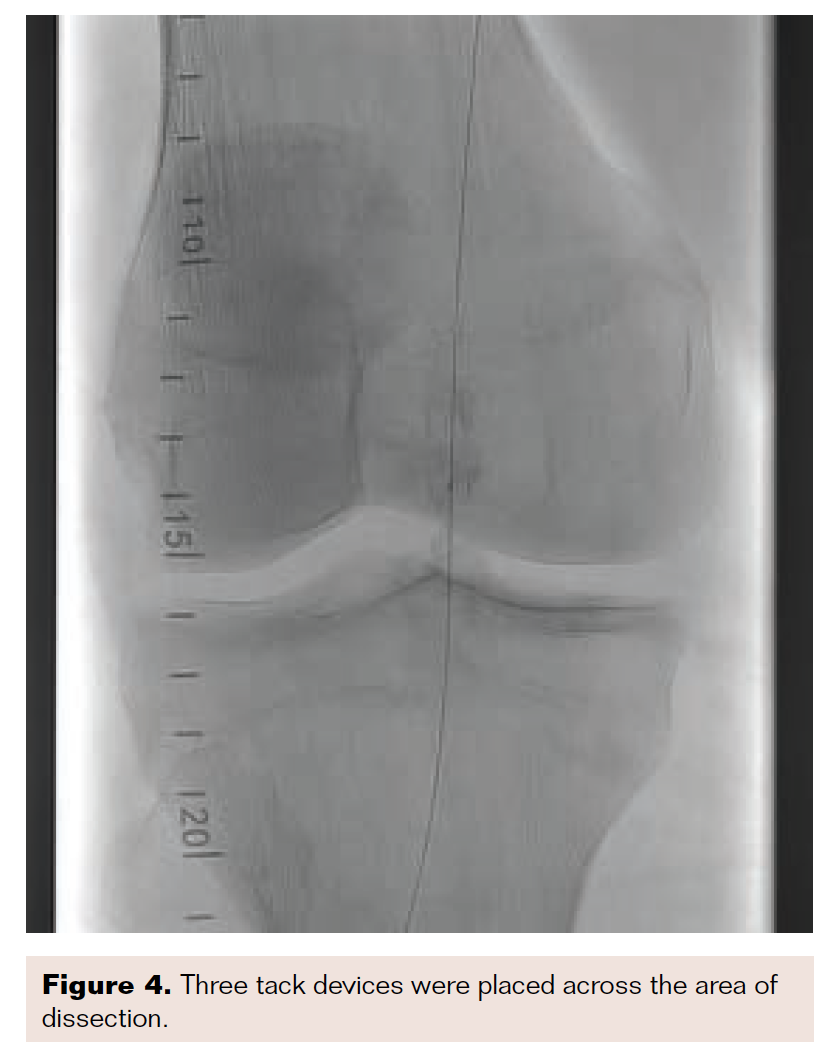

I recently treated a patient with nonhealing ulceration of his right great toe. He had a severely calcified lesion in his popliteal artery, as demonstrated in Figure 1. Due to the calcification, I performed intravascular lithotripsy with a 5.5 mm × 60 mm balloon (Figure 2). After balloon inflation, the lesion had a residual type C dissection (Figure 3). Therefore, I placed 3 tack devices across the area of dissection (Figure 4). Final angiography demonstrated no residual dissection or recoil (Figure 5).